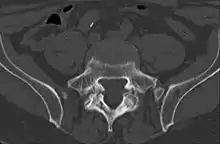

Computed tomography

Commonly known as a CT Scan or CAT scan, this form of imaging is very similar to x-ray technology but produces many more images than an x-ray does. The multiple images produce cross-sectional views not possible with an x-ray. This allows a physician or radiologist to examine the images from many more angles than an x-ray allows. For this reason the CT scan is much more accurate in detecting spondylolysis than an x-ray. Bone scintigraphy combined with CT scan is considered the gold standard which means that it is best at detecting spondylolysis.[13][15]